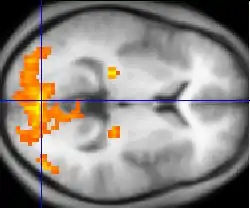

In 2012, Sorger et al. attempted to improve the previously mentioned spelling device by utilizing functional magnetic resonance imaging (fMRI).[7] The group's spelling device associated the participant's performance of certain mental tasks to a specific blood oxygenation level-dependent (BOLD) signal. BOLD signals can be used to determine which brain region activates when the participant performs a mental task.[8] The group recorded the BOLD signals for each participant for three distinct tasks: 1) motor imagery, 2) mental calculation, and 3) inner speech. The alphabet's letters were encoded with just three BOLD signals by using three task onset delays and three task durations. For example, if the patient wanted to select the letter "E", they would wait 10 seconds from the onset of the scan and then perform a motor imagery task for 30 seconds. The fMRI-based spelling device only requires about 10 to 50 seconds in order to select a specific letter of the alphabet. However, the clinical application of fMRI-based spelling devices is limited by the cost and size of MRI machines.